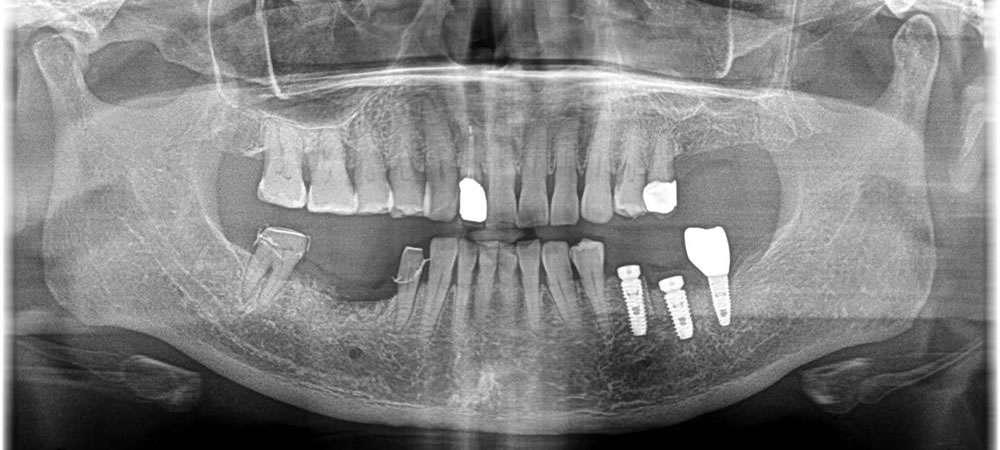

抜歯予定である歯を2本抜き、インプラント埋入、骨を作る処置までを1回で行いました。コントロールされてはいるものの、糖尿病を患っているため、術後の感染に対する対策もしっかり行いました。

骨ができるまでには6ヵ月と少し通常よりも時間がかかりましたが、しっかりと上部の歯まで作成していきました。